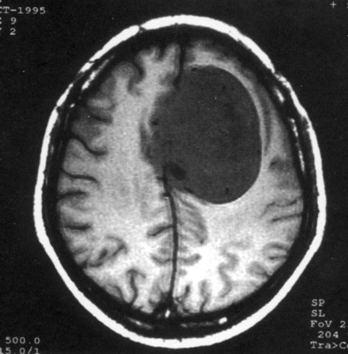

问题 病历摘要:??患者,男,40岁。发作性左下肢抽搐1年余,每次发作3~5分,每周发作1~2次。每次发作后感左下肢乏力,约半日后可自行恢复。既往身体健康。体检:神清,头顶部偏右有局限性骨性隆起(1.5×1.5cm),左鼻唇沟稍浅,伸舌居中。感觉、运动无明显异常。左浅反射减退,左下肢腱反射稍亢进,左Babinski征(-)。 下列对该患者的临床特点分析哪些是正确的?

选项 A.有Jackson癫痫发作 B.有Todd氏麻痹 C.有精神运动性癫痫发作 D.右中央前回可能有刺激性病灶存在 E.右中央后回可能有破坏性病灶存在 F.有失张力发作 G.右锥体束征(+) H.有颅内高压表现

答案 ABDG